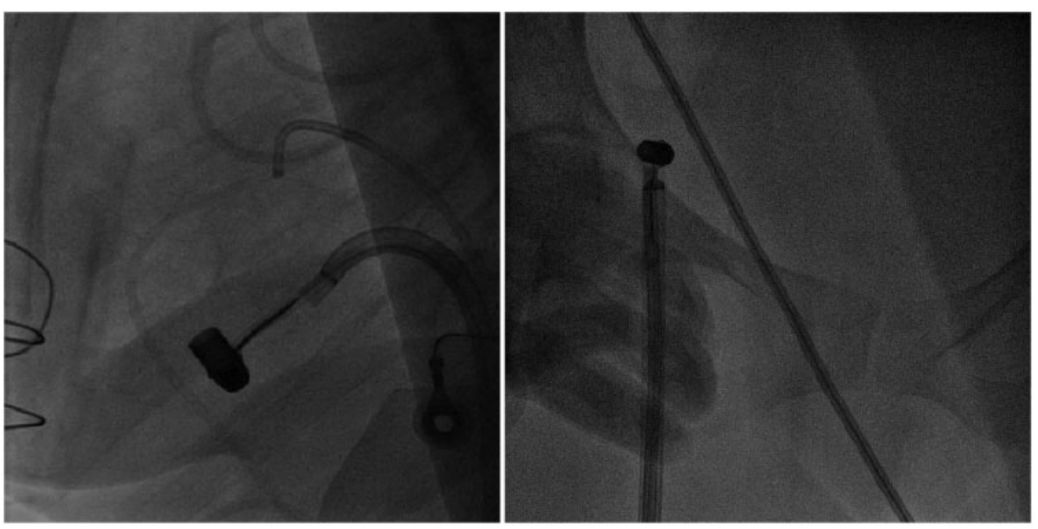

在患者清醒、镇静状态下,通过TTE引导,使用16-Fr的E鞘管进行右股静脉穿刺。在治疗时斜切鞘远端,以允许更大的流入。在本病例中之所以选择此种鞘管,是因为它可以扩展到24-Fr。

在治疗过程中,运用了下面的组件:尖端可偏转的AGILIS NXT可控导管鞘,5-Fr Judkins Right指引导管和15 mm单向鹅颈管套圈。

首先,我们试图将*弹子**从右心室腔内捕捉到三尖瓣下。此时,TEE显示三尖瓣反流由轻度增加到中度,但三尖瓣叶和瓣膜下结构未受到机械影响。

用套圈将*弹子**从外到内捕捉,以保证其适用于任何结构,如图3左;随后认真操作Agilis导管,并逆时针旋转到右心房。*弹子**进入右心房后,三尖瓣反流降低至轻度。在下腔静脉中,曾试图将整个组件与16-Fr结合,但最终以失败告终,因此将*弹子**拉至腹股沟,如图3右。

图3 左:*弹子**卡在右心室;右:用16-Fr鞘在右腹股沟捕获*弹子**